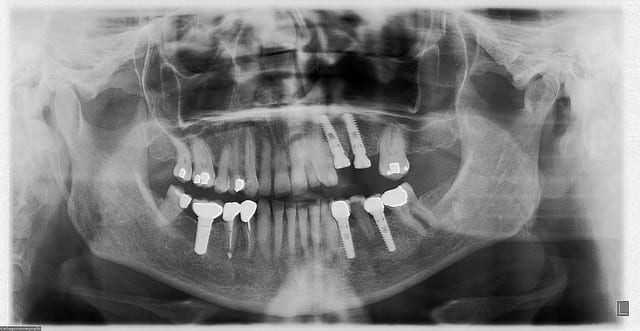

tien, ce matin, extraction de 24/25, curetage méticuleux, forage, comblement du gap, pose des 2 implants qui se sont bloqués à 50Ncm au CA sur les 3 ou 4 mm apicaux, pose des vis de cicat, sutures...35min....tranquille...

désolé, la pano est un poil déformée (la patiente à du bouger...)